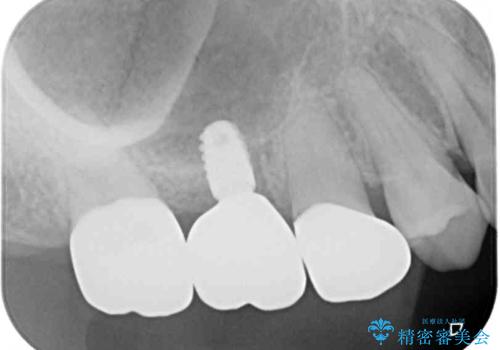

最後方歯は、クラウンを維持するための高さが不足していたため、インプラント処置の際に歯冠長を延長する手術を併用し、維持力を増すこととしました。

上顎洞までの骨高さが低いケースでしたが、ショートインプラントと骨圧縮機能を持つドリルの使用により、上顎洞底挙上を行うことなく、インプラント治療を行うことができました。